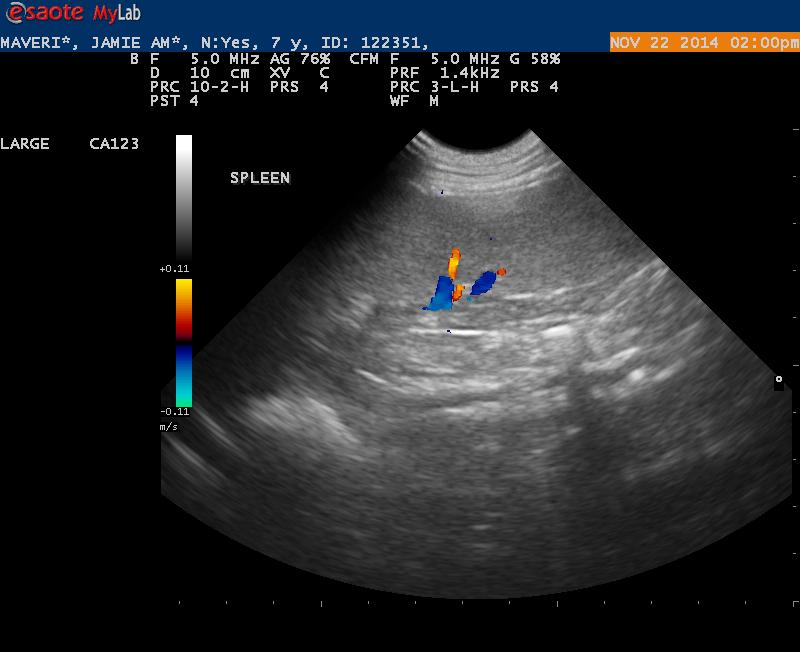

Maverick is a 7 1/2 year old Lab with 2 fairly large cutaneous mast cell tumors.

On x-rays the spleen was prominent but not overly enlarged.

Ultrasound findings were within normal limits. I did not appreciate any lymphadenopathy.

The spleen on first glance appeared to be normal- but when I went back and looked at my images I was wondering if the echotexture was a bit coarse.

1. Do you see any abnormalities with this spleen making it worthwhile to get an aspirate?